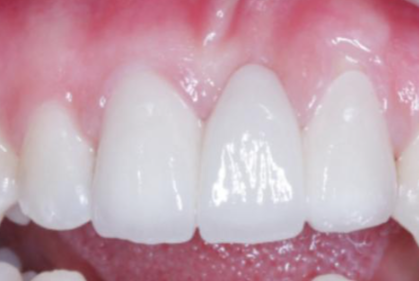

2. 精良设备支持:引进了口腔CT机、数字化口腔扫描仪、赛特丽及EMS超声洁治仪、德国kava喷砂仪、德国meleg真空消毒设备等精良设备,为医生的诊断和治疗提供精细依据,也能减少患者治疗时的痛苦和修复时间。

7. 烤瓷牙冠:300元起

11. 牙冠:880元起

12. 瓷贴面:1168元起

13. 戴妃美全瓷牙贴面:1590元左右

14. 爱尔创瓷贴面:1859元左右

15. 美加超薄瓷贴面:2980元左右

16. 美国3m拉瓦全瓷贴面:2899元左右

17. 全瓷牙套:740 - 5099元左右